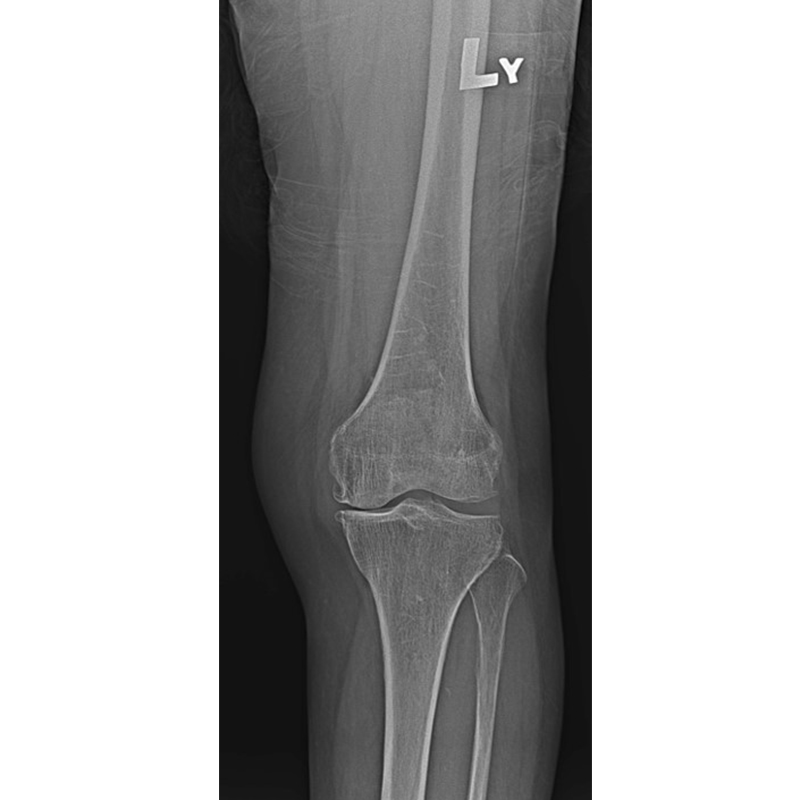

傳統全膝關節置換 首頁 案例分享 膝關節手術 傳統全膝關節置換 江女士 61歲 術前 術後 劉先生 83歲 術前 術後 70歲 柯先生 術前 術後 75歲 黃女士 術前 術後 77歲 羅女士 術前 術後